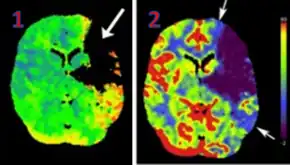

CT perfusion with flow and volume maps in cerebral infarction | |

Perfusion CT or CT Perfusion is a type of Perfusion Scanning using Computed Tomography. It is helpful in evaluation of the vascularity of a tissue in the body. In this the temporal changes in the tissue density are measured which gives the information about the vascularity of the tissue. In CT perfusion injection of contrast media is given and then the scan is taken. The acquired data are then post-processed to obtain perfusion maps with different parameters, such as BV (blood volume), BF (blood flow), MTT (mean transit time) and TTP (time to peak).[1][2]

CT Perfusion plays an important role in the assessment of Acute Ischemia Stroke. It is used to create maps of blood flow, blood volume and mean transit time to assess the tissue and to differentiate between core and penumbra in stroke.[3]